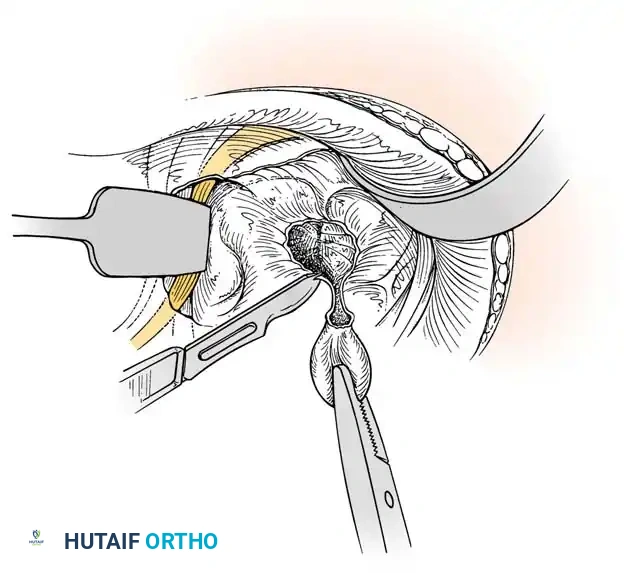

- Neurectomy: Identify the terminal sensory fibers of the posterior interosseous nerve (PIN) at the floor of the fourth compartment. Divide the nerve and gently cauterize the proximal end to denervate the dorsal capsule and reduce postoperative pain.

Cauterization of the capsular margins and the terminal branches of the posterior interosseous nerve.

- Closure: Deflate the tourniquet, irrigate the wound copiously, and obtain meticulous hemostasis. Do not close the joint capsule. Close the skin with a running, subcuticular 4-0 nylon or Monocryl suture. Apply a sterile compressive dressing and a volar splint.